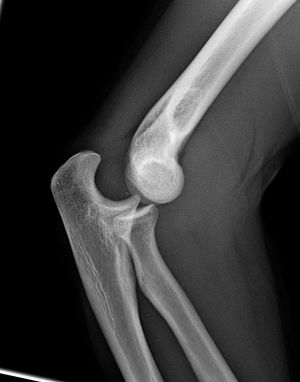

팔꿉관절(주관절)은 상완골, 요골, 척골 사이에 존재하는 관절이다. 굽힘과 폄(굴신)을 행하는 것은 주로 위팔뼈와 척골 사이이다.

팔꿈치 관절은 공통 관절낭으로 둘러싸인 세 개의 다른 부분으로 구성되어 있다. 이들은 상완의 상완골, 전완의 요골와 척골 사이의 관절이다.| 관절 | 에서 | 로 | 설명 |

해부학적 자세에서 팔꿈치에는 네 개의 주요 뼈대 랜드마크가 있다. 상완골의 하단에는 몸에 가장 가까운 쪽(내측)과 몸에서 가장 먼 쪽(외측) 표면에 있는 상완골 내측 상과와 상완골 외측 상과가 있다. 세 번째 랜드마크는 자뼈 머리에서 발견되는 주두이다. 이들은 ''Hueter 선''이라고 하는 수평선상에 놓여 있다. 팔꿈치가 굴곡될 때, 이들은 정삼각형과 유사한 ''Hueter 삼각형''이라고 하는 삼각형을 형성한다.[5]

팔꿈치 관절의 기능은 팔을 뻗고 구부리고 물건을 잡는 것이다. 팔꿈치의 움직임 범위는 팔꿈치 확장 0도부터 팔꿈치 굴곡 150도까지이다. 기능에 기여하는 근육은 굴곡근(상완이두근, 상완근, 상완요골근) 및 신전 근육(삼두근, 주근)이 있다.[10]인간의 경우 팔꿈치의 주요 임무는 상지를 단축시키고 늘려 손을 공간에 적절하게 배치하는 것이다. 위아래노자관절(상 요척골 관절)은 팔꿈치 관절과 관절낭을 공유하지만 팔꿈치에서는 기능적 역할을 하지 않는다.

팔꿈치를 펴면 위팔뼈(상완골)의 장축과 척골의 장축이 일치한다. 동시에 두 뼈의 관절 표면은 해당 축 앞에 위치하며 45° 각도로 벗어난다. 또한, 팔꿈치에서 시작되는 팔뚝 근육은 관절의 측면에 모여 움직임을 방해하지 않는다. 이 배열로 인해 가능해진 팔꿈치의 넓은 굴곡 각도(거의 180°)로 인해 뼈가 서로 거의 평행하게 될 수 있다.